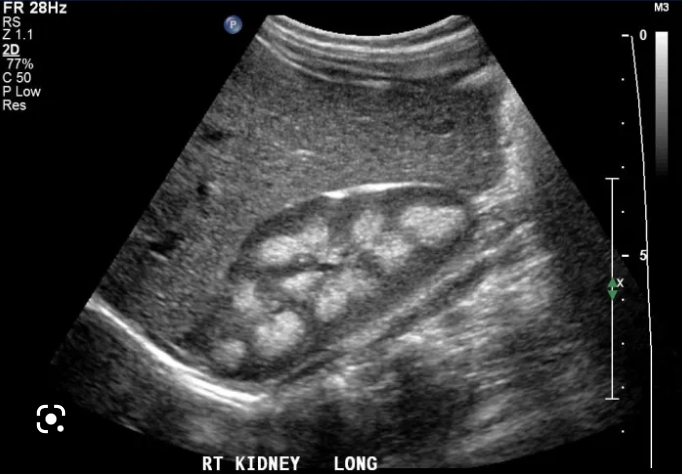

A

Medullary nephrocalcinosis

Note: Hyperechoic renal papilla/pyramids (may or may not shadow on ultrasound).

Common causes of medullary nephrocalcinosis

• Hyperparathyroidism (most common)

• Medullary sponge kidney (second most common)

• Lasix use

• Renal tubular acidosis type 1

Note: Hyperparathyroidism and type 1 RTA tend to cause more dense calcification than medullary sponge.